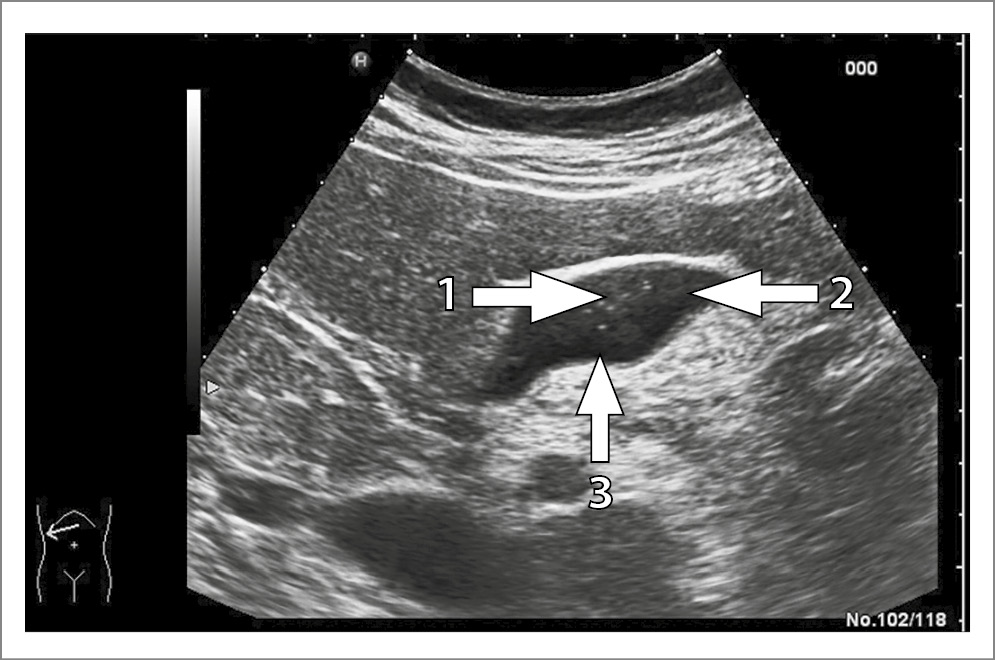

Актуальность ЖКБ в структуре заболеваний гастроэнтерологического профиля подчеркивается не только широким распространением данного заболевания, достигающим 20% в мировой взрослой популяции, но и риском осложненного течения, требующего оперативного вмешательства [2, 3]. БС, входящий в континуум ЖКБ, рассматривается как ступень, предшествующая формированию холестериновых камней, успешно поддающаяся лекарственной терапии [7, 19]. Основным методом диагностики БС является трансабдоминальное ультразвуковое исследование, позволяющее дифференцировать тип сладж- синдрома. Так, 1-й тип представляет собой взвесь маленьких, точечных и смещаемых гиперэхогенных частиц без акустической тени, выявляемых при изменении положения тела пациента (рис. 4).

Рис. 4. Билиарный сладж 1-го типа: 1 – гиперэхогенные включения в полости желчного пузыря.

Для 2-го типа характерна эхонеоднородная желчь с наличием сгустков различной эхогенности с четкими или размытыми контурами, не дающих акустической тени. Тип 3 определяется при сочетании эхонеоднородной густой желчи со сгустками, иногда дающими акустическую тень, с микролитиазом (рис. 5) [10].

Рис. 5. Билиарный сладж 3-го типа: 1 – гиперэхогенные включения; 2 – сгустки эхонеоднородной желчи; 3 – слой менее густой, более однородной желчи.